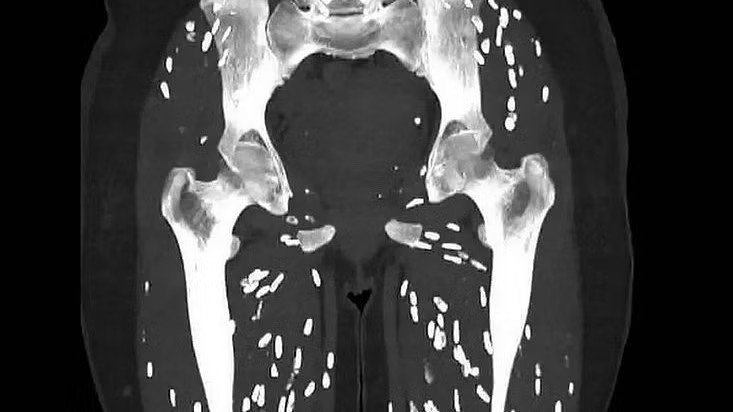

H́nh chụp chân của người bệnh chi chít kư sinh trùng khiến bác sĩ thốt lên “đây là một trong số các bản chụp đáng sợ nhất” mà ông từng thấy.

Tiến sĩ Ghali đăng h́nh CT chân của người bệnh kèm chú thích: "Đây là một trong những bản chụp đáng sợ nhất mà tôi từng thấy". Phim cho thấy sự hiện diện của bệnh sán dây do Taenia solium (sán dây lợn) gây ra.

Phim chụp chân cho thấy bệnh nhân nhiễm sán dây lợn. Nguồn: Em_resus

“Người bệnh ăn phải nang sán trong thịt lợn nấu chưa chín. Sau vài tuần (khoảng 5-12 tuần), những nang sán đó phát triển trong đường tiêu hóa thành sán dây trưởng thành tiếp tục đẻ trứng. T́nh trạng này được gọi là bệnh sán dây ruột”, Tiến sĩ Ghali giải thích.